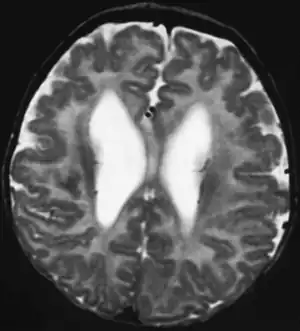

| This child presented with seizures. The coronal true inversion recovery sequence shows thickened and disordered cortex in superior frontal and cingulate gyri bilaterally (arrow). There are small convolutions visible at the corticomedullary junction. The appearance is that of cortical dysplasia, with polymicrogyria more likely than pachygyria due to the small convolutions visible. There are also small foci of grey matter signal in the corpus callosum, deep to the dysplastic cortex (double arrows). These probably represent areas of grey matter heterotopia. | |

Pathologically, PMG is defined as "an abnormally thick cortex formed by the piling upon each other of many small gyri with a fused surface."[14] To view these microscopic characteristics, magnetic resonance imaging (MRI) is used. First physicians must distinguish between polymicrogyria and pachygyria. Pachygria leads to the development of broad and flat regions in the cortical area, whereas the effect of PMG is the formation of multiple small gyri. Underneath a computerized tomography (CT scan) scan, these both appear similar in that the cerebral cortex appears thickened. However, MRI with a T1 weighted inversion recovery will illustrate the gray-white junction that is characterized by patients with PMG.[13] An MRI is also usually preferred over the CT scan because it has sub-millimeter resolution. The resolution displays the multiple folds within the cortical area, which is continuous with the neuropathology of an infected patient.